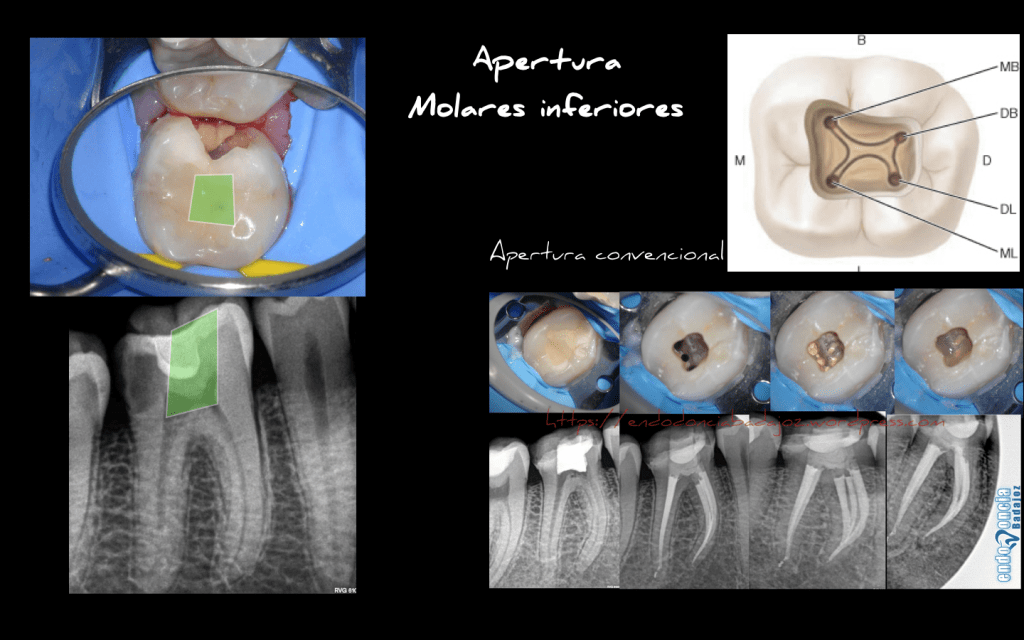

Apertura en los molares inferiores.

Se trata de un molar inferior , que con una apertura convencional, eliminaríamos la caries distal más la apertura convencional, dejando una estructura dentinaria bastante pobre, como podemos ver en otros casos:

Captura de pantalla 2016-06-21 a las 20.18.06

Lo que intentamos es estudiar el caso, como cualquier otra especialidad odontológica, para ver de que manera es la más beneficiosa para el paciente, sabiendo que debemos realizar un tratamiento endodóntico correcto y eficaz, pero que por desgracia depende en gran medida de la estructura remanente dentinaria , por lo que también debemos pensar en ello.

Así que , teniendo presente la complejidad anatomica de estas piezas, por lo que no en todas las piezas lo podemos hacer ( de ahí, que debamos estudiar el caso), decidimos intentar ser lo más conservador posible intentando conseguir  un equilibrio entre en un buen tratamiento de conductos y mantener la mayor cantidad de tejido dentinario.